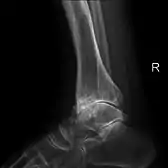

Diagnosis is made with reasonable certainty based on history and clinical examination.[51][52] X-rays may confirm the diagnosis. The typical changes seen on X-ray include: joint space narrowing, subchondral sclerosis (increased bone formation around the joint), subchondral cyst formation, and osteophytes.[53] Plain films may not correlate with the findings on physical examination or with the degree of pain.[54]

Severe osteoarthritis and osteopenia of the carpal joint and 1st carpometacarpal joint